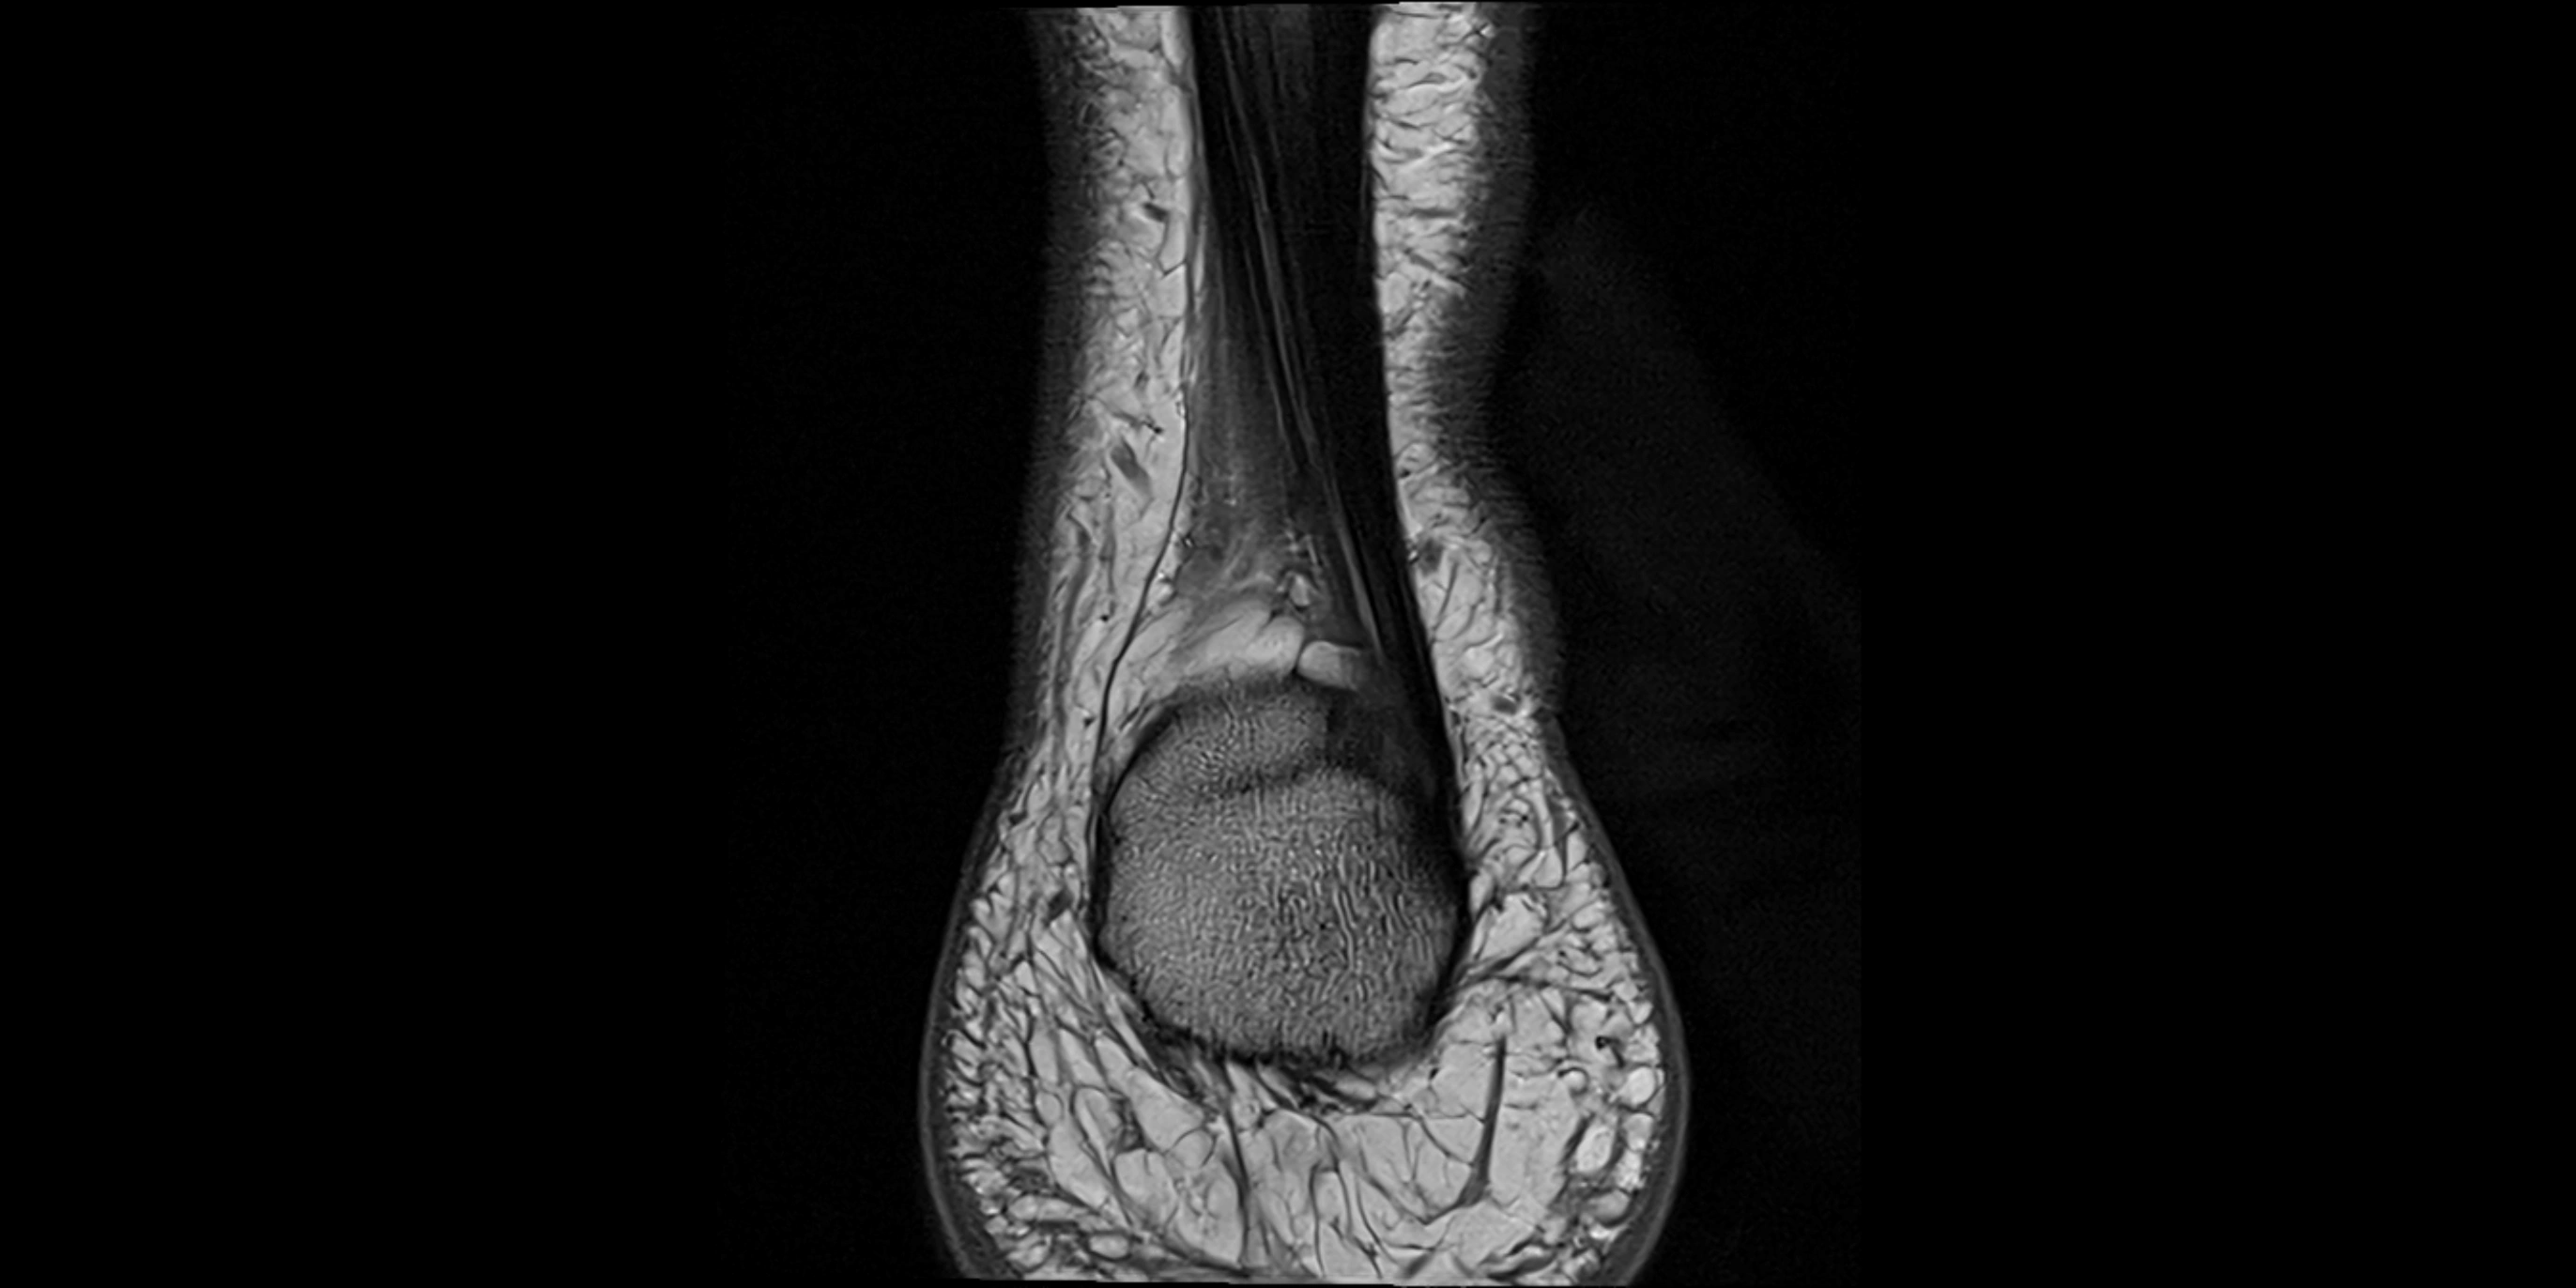

MRI image

image